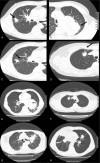

Distinguishing lung adenocarcinoma from squamous cell carcinoma (SCC) is clinically important. Computed tomography (CT) scan is an economical, effective, noninvasive, commonly available, and quick diagnostic way for lung cancer. In this study, we aim to compare the CT characteristics in adenocarcinoma and SCC.Data from 275 cases (259 adenocarcinoma and 16 SCC) were retrospectively compared. CT characteristics, including lesion size and shape, single/multifocal lesions, location of the tumor, the margin of lobes, whether the lesion had deep lobulated margin, bronchial cut-off sign, signs of dilated bronchial arteries, signs of vascular bundle thickening, signs of short burrs, spinous processes, and pleural indentation, were compared in 148 cases (137 adenocarcinoma and 11 SCC).Patients with adenocarcinoma were more likely to be female (44.2% vs 25.0%, P = .017). Compared with SCC, adenocarcinomas were more likely to have deep lobulated margin (81.0% vs 54.5%, P = .038), less likely to have smooth lobes margin (2.7% vs 83.3%, P < .001), more likely to have vascular bundle thickening (37.2% vs 0, P = .016) and pleural indentation (59.9% vs 18.2%, P = .01), and marginally less likely to have dilated bronchial arteries (17.5% vs 45.5%, P = .064). No significant difference was observed regarding to characteristics, including tumor size, location of the tumor, signs of bronchial cut-off, dilated bronchial arteries, short burrs, or spinous processes.CT scan has the potential to help to distinguish lung adenocarcinoma and SCC in a fast and commonly available way. CT could be a rough but fast way to diagnosis, and may thus shorten the waiting time to treatment and allow more time for clinicians, patients, and their families to prepare for future treatment.